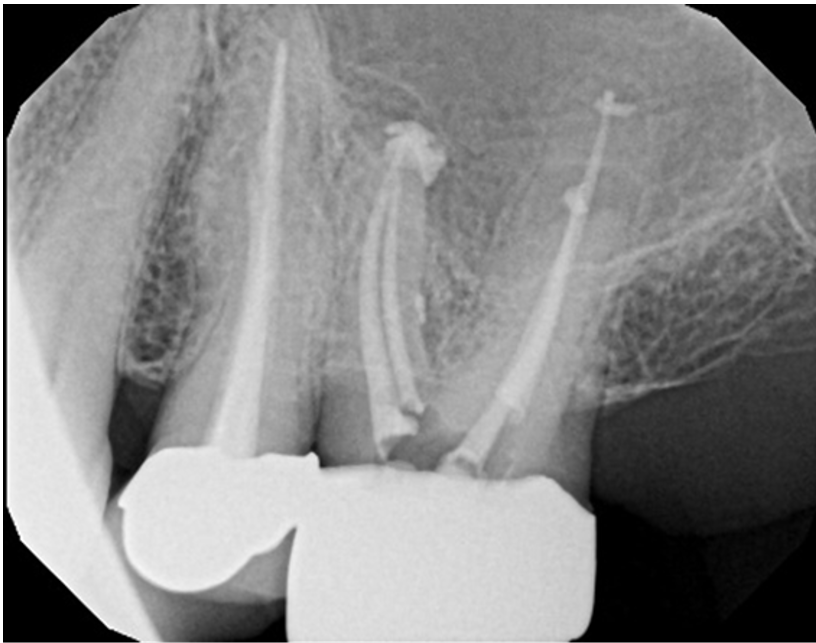

Examples of X-Ray scoring

(Group A – Odne Clean)

Score 4 – Simple anatomy with apical delta // Score 6 – Curved anatomy + lateral canal in middle third

Score 7 – Curved anatomy + lateral canal in apical third // Score 8 – Curved anatomy with apical delta